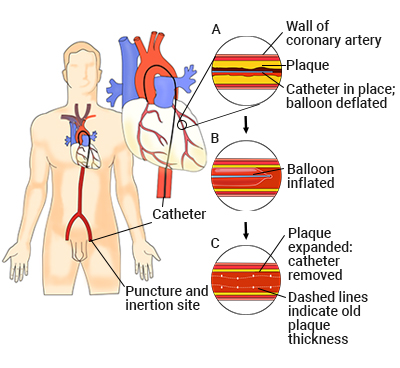

Overview

Package includes:

Days in hospital : 3 to 4 Days (For patient and one attendant)

Days in hotel : 7 Days (For patient and one attendant)

Room type in hospital : Shared

Room type in hotel : Private

Hotel category: Standard

Value added benefits of the Coronary Angioplasty:

Ø Doctor consultation charges

Ø Lab tests and diagnostic charges

Ø Room charges inside hospital during the procedure

Ø Surgeon Fee

Ø Nursing charges

Ø Hospital surgery suite charges

Ø Anesthesia charges

Ø Routine medicines and routine consumables (bandages, dressings etc.)

Ø Food and Beverages inside hospital stay for patient and one attendant.

Extra benefits:

ü Interpreter

ü Visa assistance

Ø Site tourism of the city

Ø Follow up with the doctor

Ø Airport pick up and drop

Ø Free online consultation with the doctor

Ø Priority appointments with the doctor

Ø Room upgrade from sharing to private

Overview

Package includes:

Days in hospital : 3 to 4 Days (For patient and one attendant)

Days in hotel : 7 Days (For patient and one attendant)

Room type in hospital : Shared

Room type in hotel : Private

Hotel category: Standard

Value added benefits of the Angioplasty PTCA :

Ø Doctor consultation charges

Ø Lab tests and diagnostic charges

Ø Room charges inside hospital during the procedure

Ø Surgeon Fee

Ø Nursing charges

Ø Hospital surgery suite charges

Ø Anesthesia charges

Ø Routine medicines and routine consumables (bandages, dressings etc.)

Ø Food and Beverages inside hospital stay for patient and one attendant.

Extra benefits:

ü Interpreter

ü Visa assistance

Ø Site tourism of the city

Ø Follow up with the doctor

Ø Airport pick up and drop

Ø Free online consultation with the doctor

Ø Priority appointments with the doctor

Ø Room upgrade from sharing to private

Overview

Package includes:

Days in hospital : 2 to 3 Days (For patient and one attendant)

Days in hotel : 14 Days (For patient and one attendant)

Room type in hospital : Shared

Room type in hotel : Private

Hotel category: Standard

Value added benefits of the Percutaneous transluminal coronary angioplasty (PTCA):

Ø Doctor consultation charges

Ø Lab tests and diagnostic charges

Ø Room charges inside hospital during the procedure

Ø Surgeon Fee

Ø Nursing charges

Ø Hospital surgery suite charges

Ø Anesthesia charges

Ø Routine medicines and routine consumables (bandages, dressings etc.)

Ø Food and Beverages inside hospital stay for patient and one attendant.

Extra benefits:

ü Interpreter

ü Visa assistance

Ø Site tourism of the city

Ø Follow up with the doctor

Ø Airport pick up and drop

Ø Free online consultation with the doctor

Ø Priority appointments with the doctor

Ø Room upgrade from sharing to private